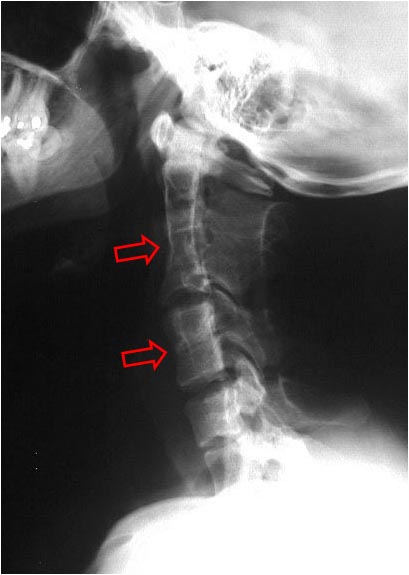

SIGNO DE LA PAJARITA AUSENTE

En los cortes sagitales de resonancia magnética de la rodilla, el cuerpo del menisco normal se parece a una pajarita (o corbata de lazo), es decir, se ven dos triángulos que apuntan uno al otro y se unen en el centro. Con cortes de 5 mm, debe verse en dos cortes consecutivos.

El signo de la pajarita ausente consiste en que el cuerpo del menisco es visible en menos de dos cortes consecutivos. Esto indica que existe una rotura longitudinal del cuerpo meniscal con desplazamiento del fragmento interno (rotura «en asa de cubo»).

Arriba a la izquierda: plano axial que muestra los meniscos normales. Arriba a la derecha: esquema de una rotura en “asa de cubo” del menisco externo. Las líneas rojas representan los planos de corte coronal.

Abajo a la izquierda: esquema del corte coronal en el menisco normal en el que se ve la imagen de pajarita. Abajo a la derecha: el signo de la pajarita ausente en la rotura meniscal.

Más información en Lieberman, KA. The absent bow tie sign. Radiology 2000; 215: 263-265.

y en este enlace: http://www.gentili.net/signs/91.htm.